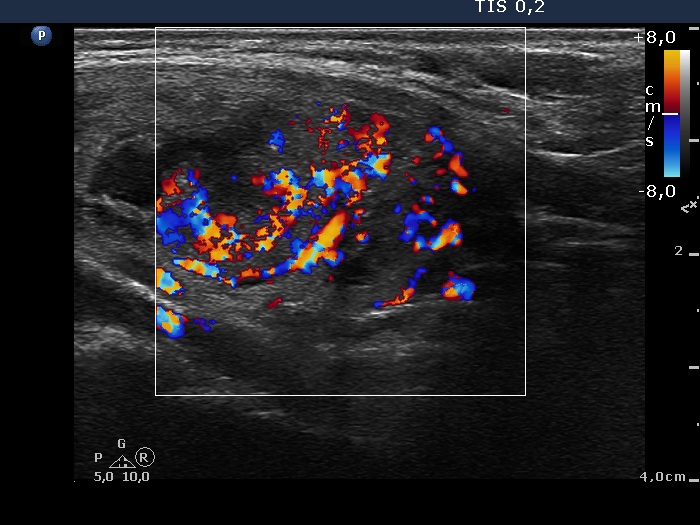

Intranodular hyperechogenic figures - case 951 (ultrasonographic picture 5)

Right lobe, longitudinal view, color Doppler mode. Left the upper cystic, right the hypoechogenic nodule.